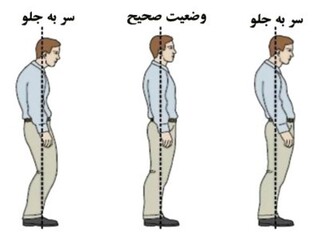

/فیلم آموزشی /

ناهنجاری سر به جلو

رحمت اله خان محمدی/مسئول حرکات اصلاحی هیات پزشکی ورزشی استان خوزستان

ناهنجاری سر به جلو

سبک زندگی امروزی باعث شده بیشتر افراد در طول شبانه روز ساعت ها در وضعیت هایی قرار بگیرند که در آن وضعیت ها فشار مضاعفی به ستون فقرات بویژه ناحیه گردن وارد شود.